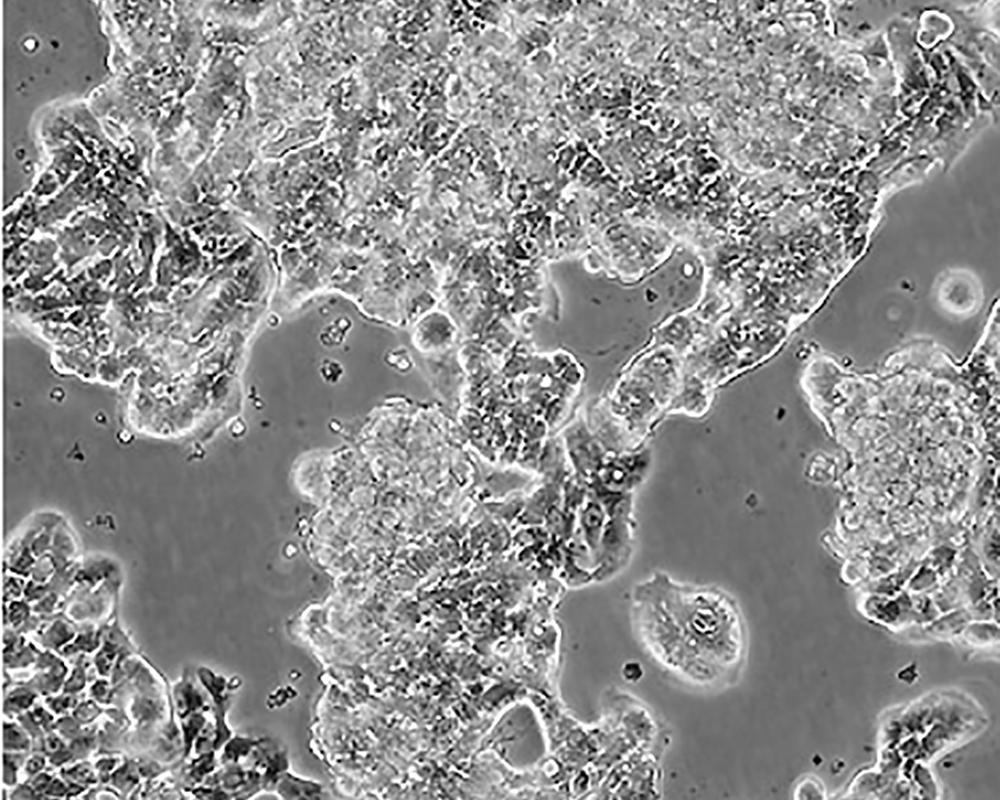

產品名稱 ZR-75-1 [ZR751]

商品貨號 MZ-0194

中文名稱 人乳腺癌細胞

組織來源 浸潤性導管癌;腹水轉移;女性

生長特性 adherent

形態特征 epithelial

細胞描述 該細胞產生高水平的黏液素MUC-1 mRNA,低水平的MUC-2 mRNA,但不表達MUC-3基因;表達雌激素受體。